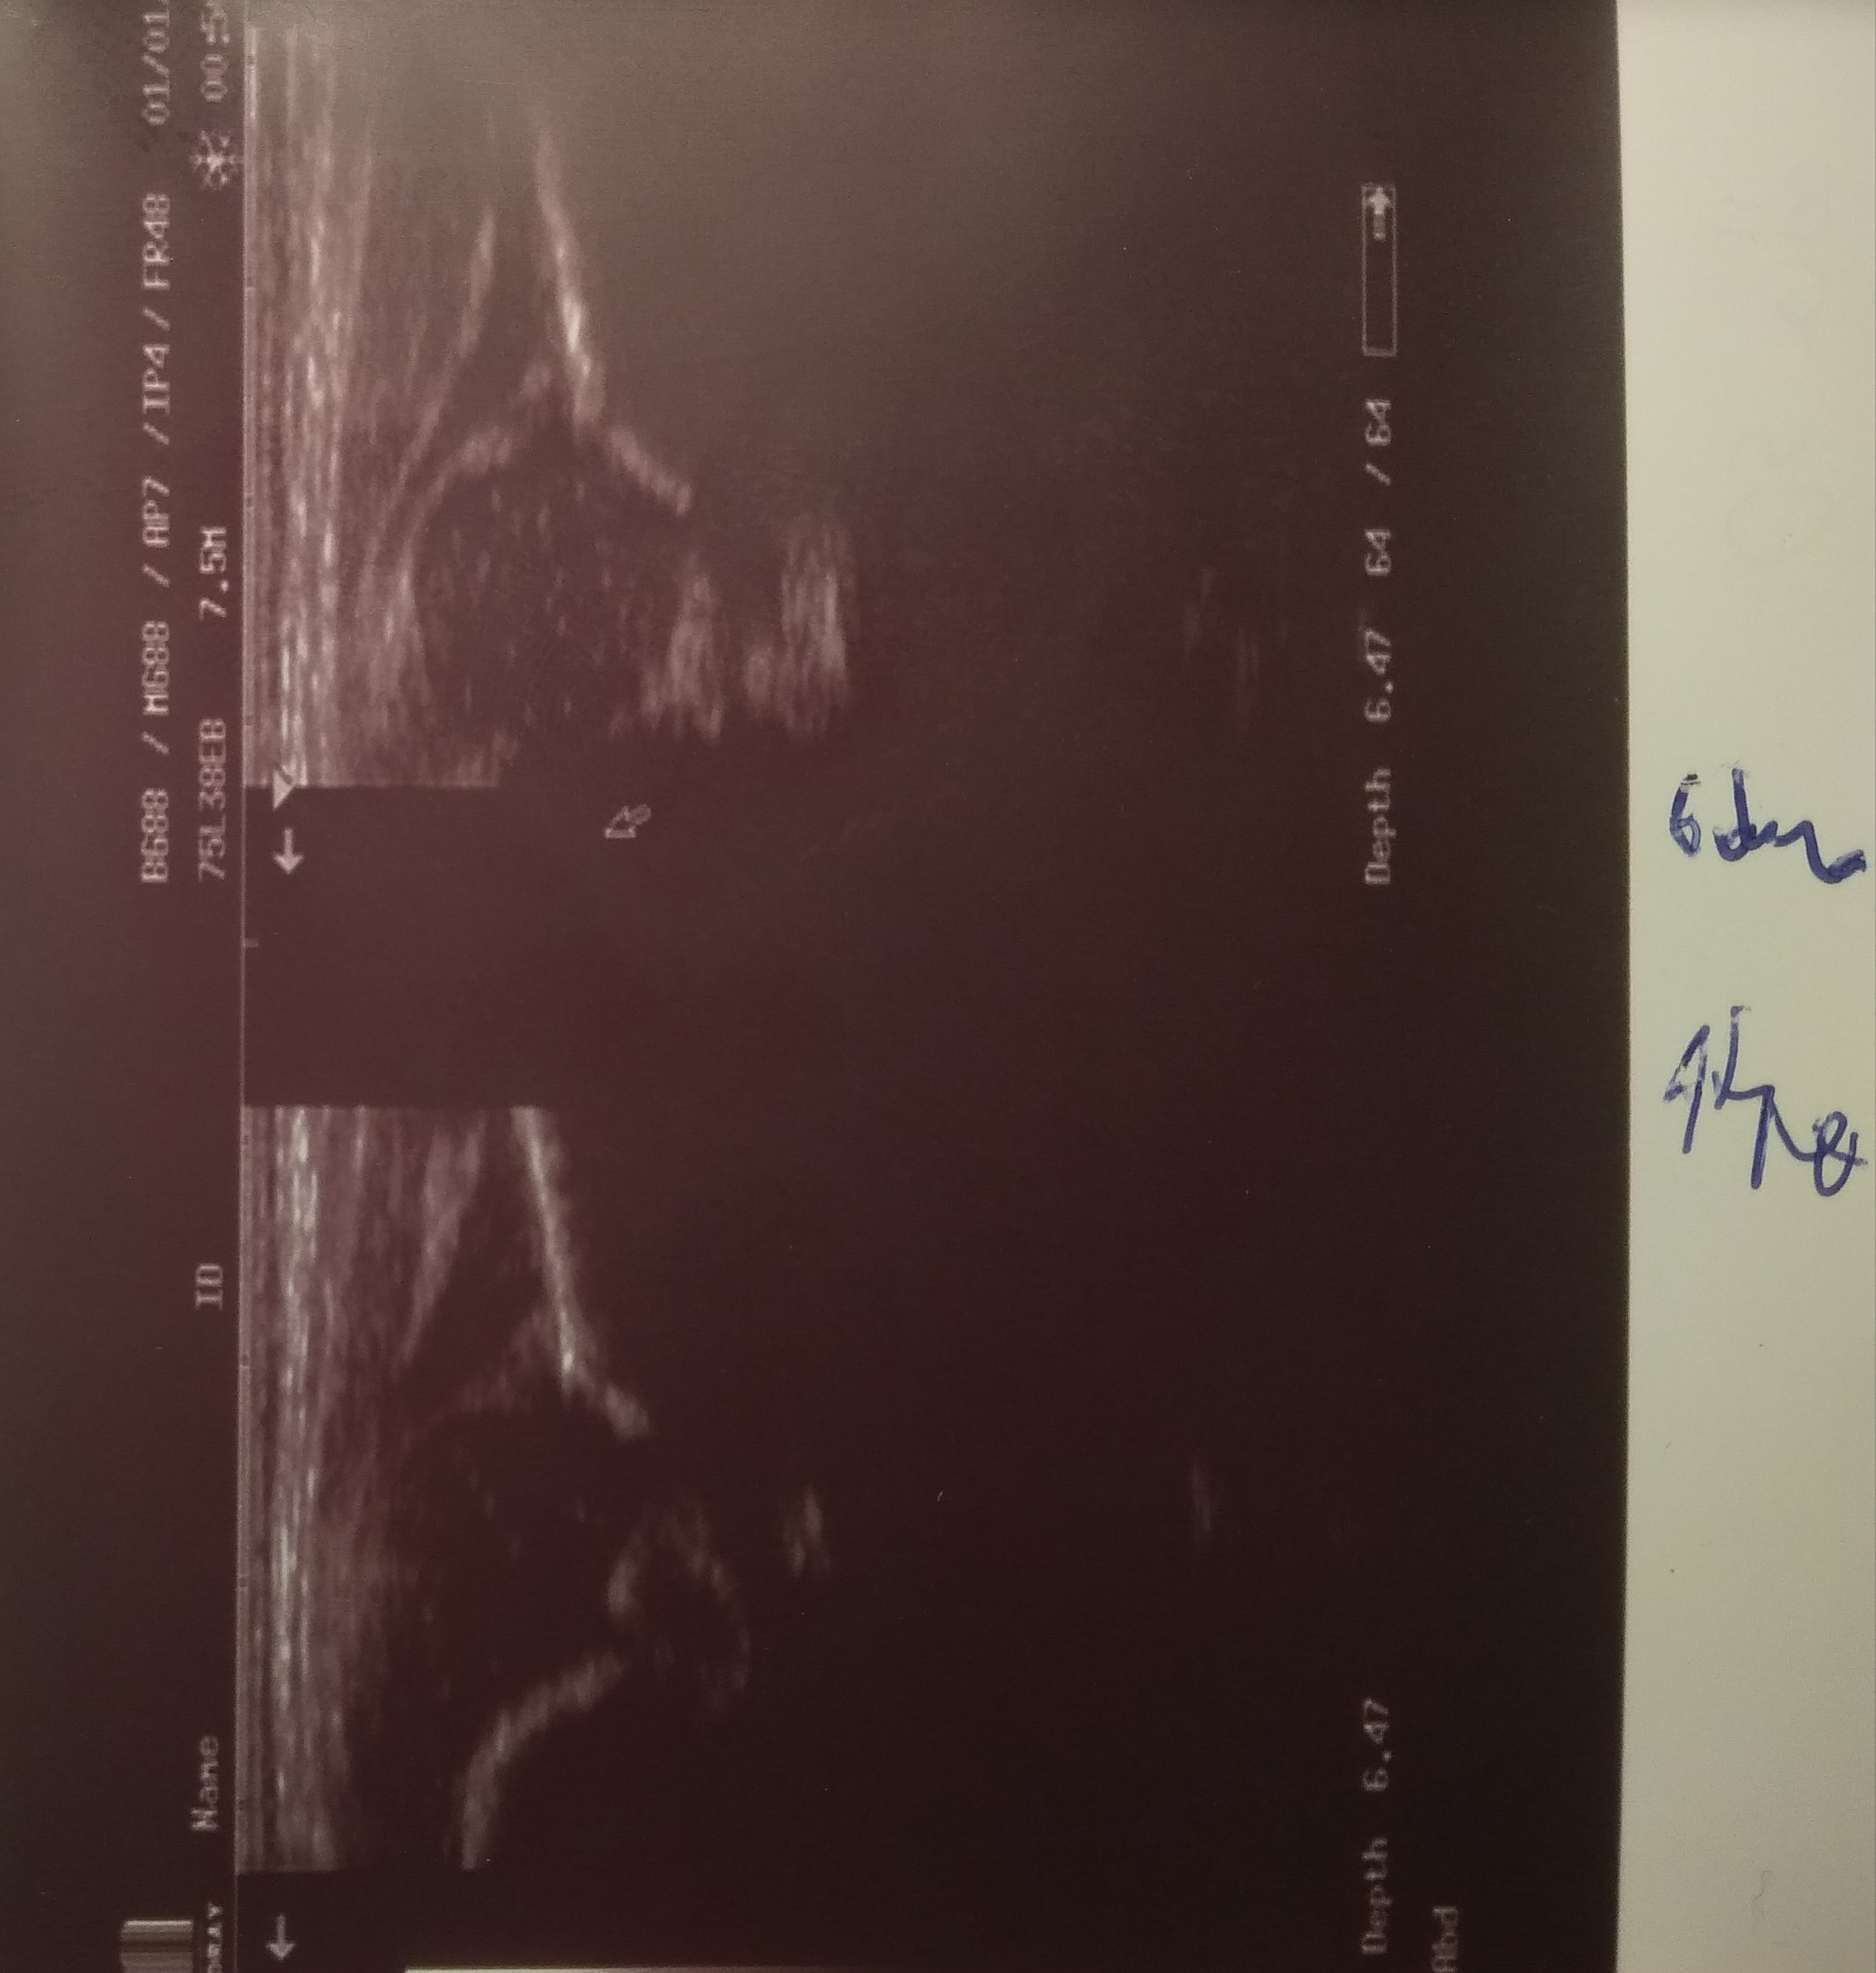

oria Anna 6 dni wtorek

typ P :D L: III/IV biodra niestabilne obustronnie rozpoznana po porodzie na oddziale noworodkowym zlecono usg za dwa tygodnie (brak stadandartów postepowania) ;

przyszła szybciej

profilatyka prowdzona przez rodziców bez przerwy przez całą dobę

7 dzien zycia środa dzien póżniej Typ P IIIa L D widac juz poprawe dalej profilaktyka kontrola w nastepnym dniu

8 dzien czwartek protilaktyka dalej 24 godz na dobę

TYP P IIA L D (gorny L) kontrola za 2 dni